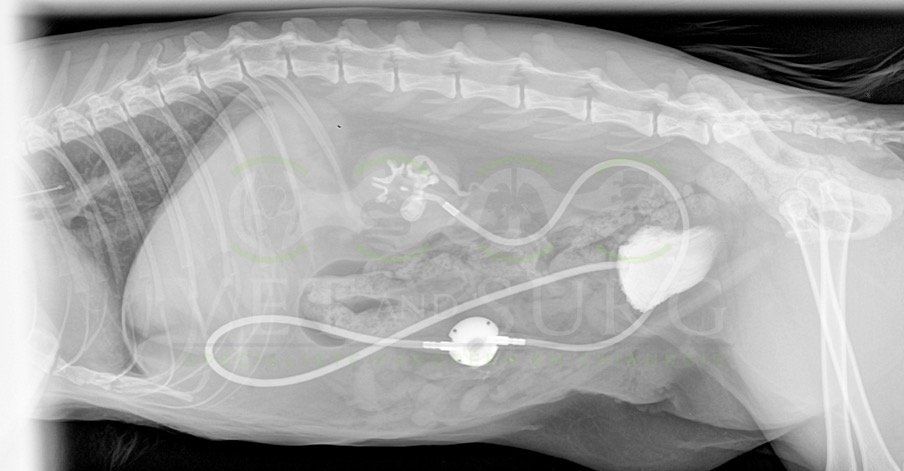

Obstruction urétérale chez un chat Sacré de birmanie de 8 ans

Hutch, chat Sacré de Birmanie de 8 ans, a été présenté en consultation pour abattement et vomissements depuis quelques jours.

A l'échographie abdominale, une dilatation de la cavité pyélique rénale gauche est mise en évidence, avec présence de calculs obstructifs dans l'uretère gauche.

Une pose de SUB a été effectuée, reliant la cavité pyélique gauche à la vessie, en court-circuitant l'uretère obstrué.